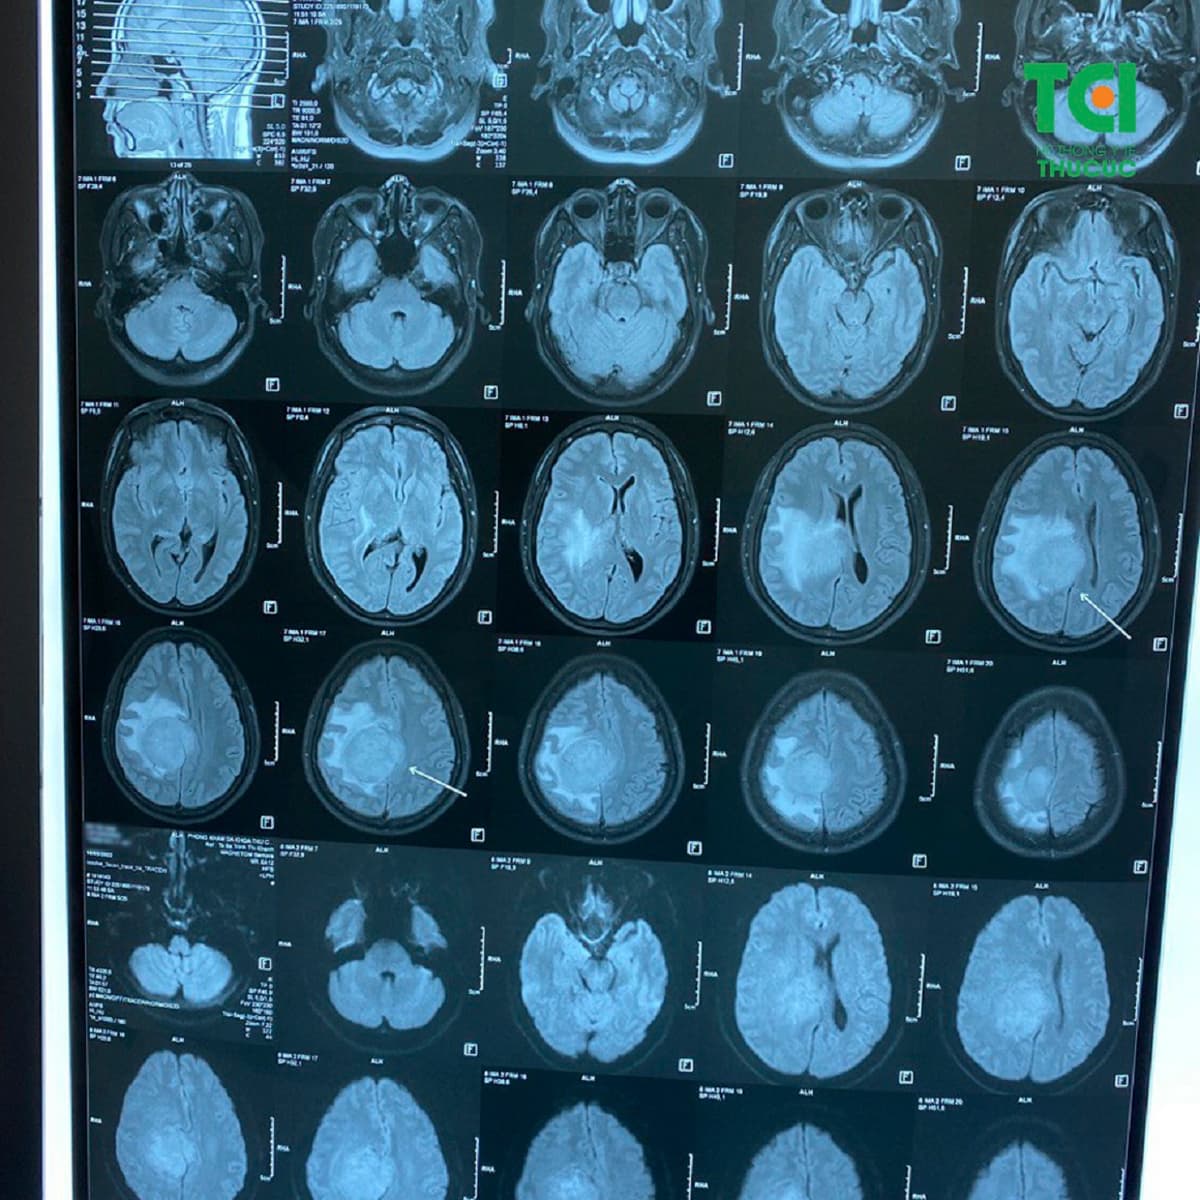

Phục hồi sau tai biến mạch máu não rất quan trọng

Tai biến mạch máu não (đột quỵ) để lại hậu quả vô cùng nặng nề. Khoảng ½ số người còn sống sau cơn tai biến mạch máu não, trong đó có đến hơn 90% phải chung sống với một hoặc nhiều di chứng, có thể đeo bám đến suốt đời như: liệt vận động, rối […]